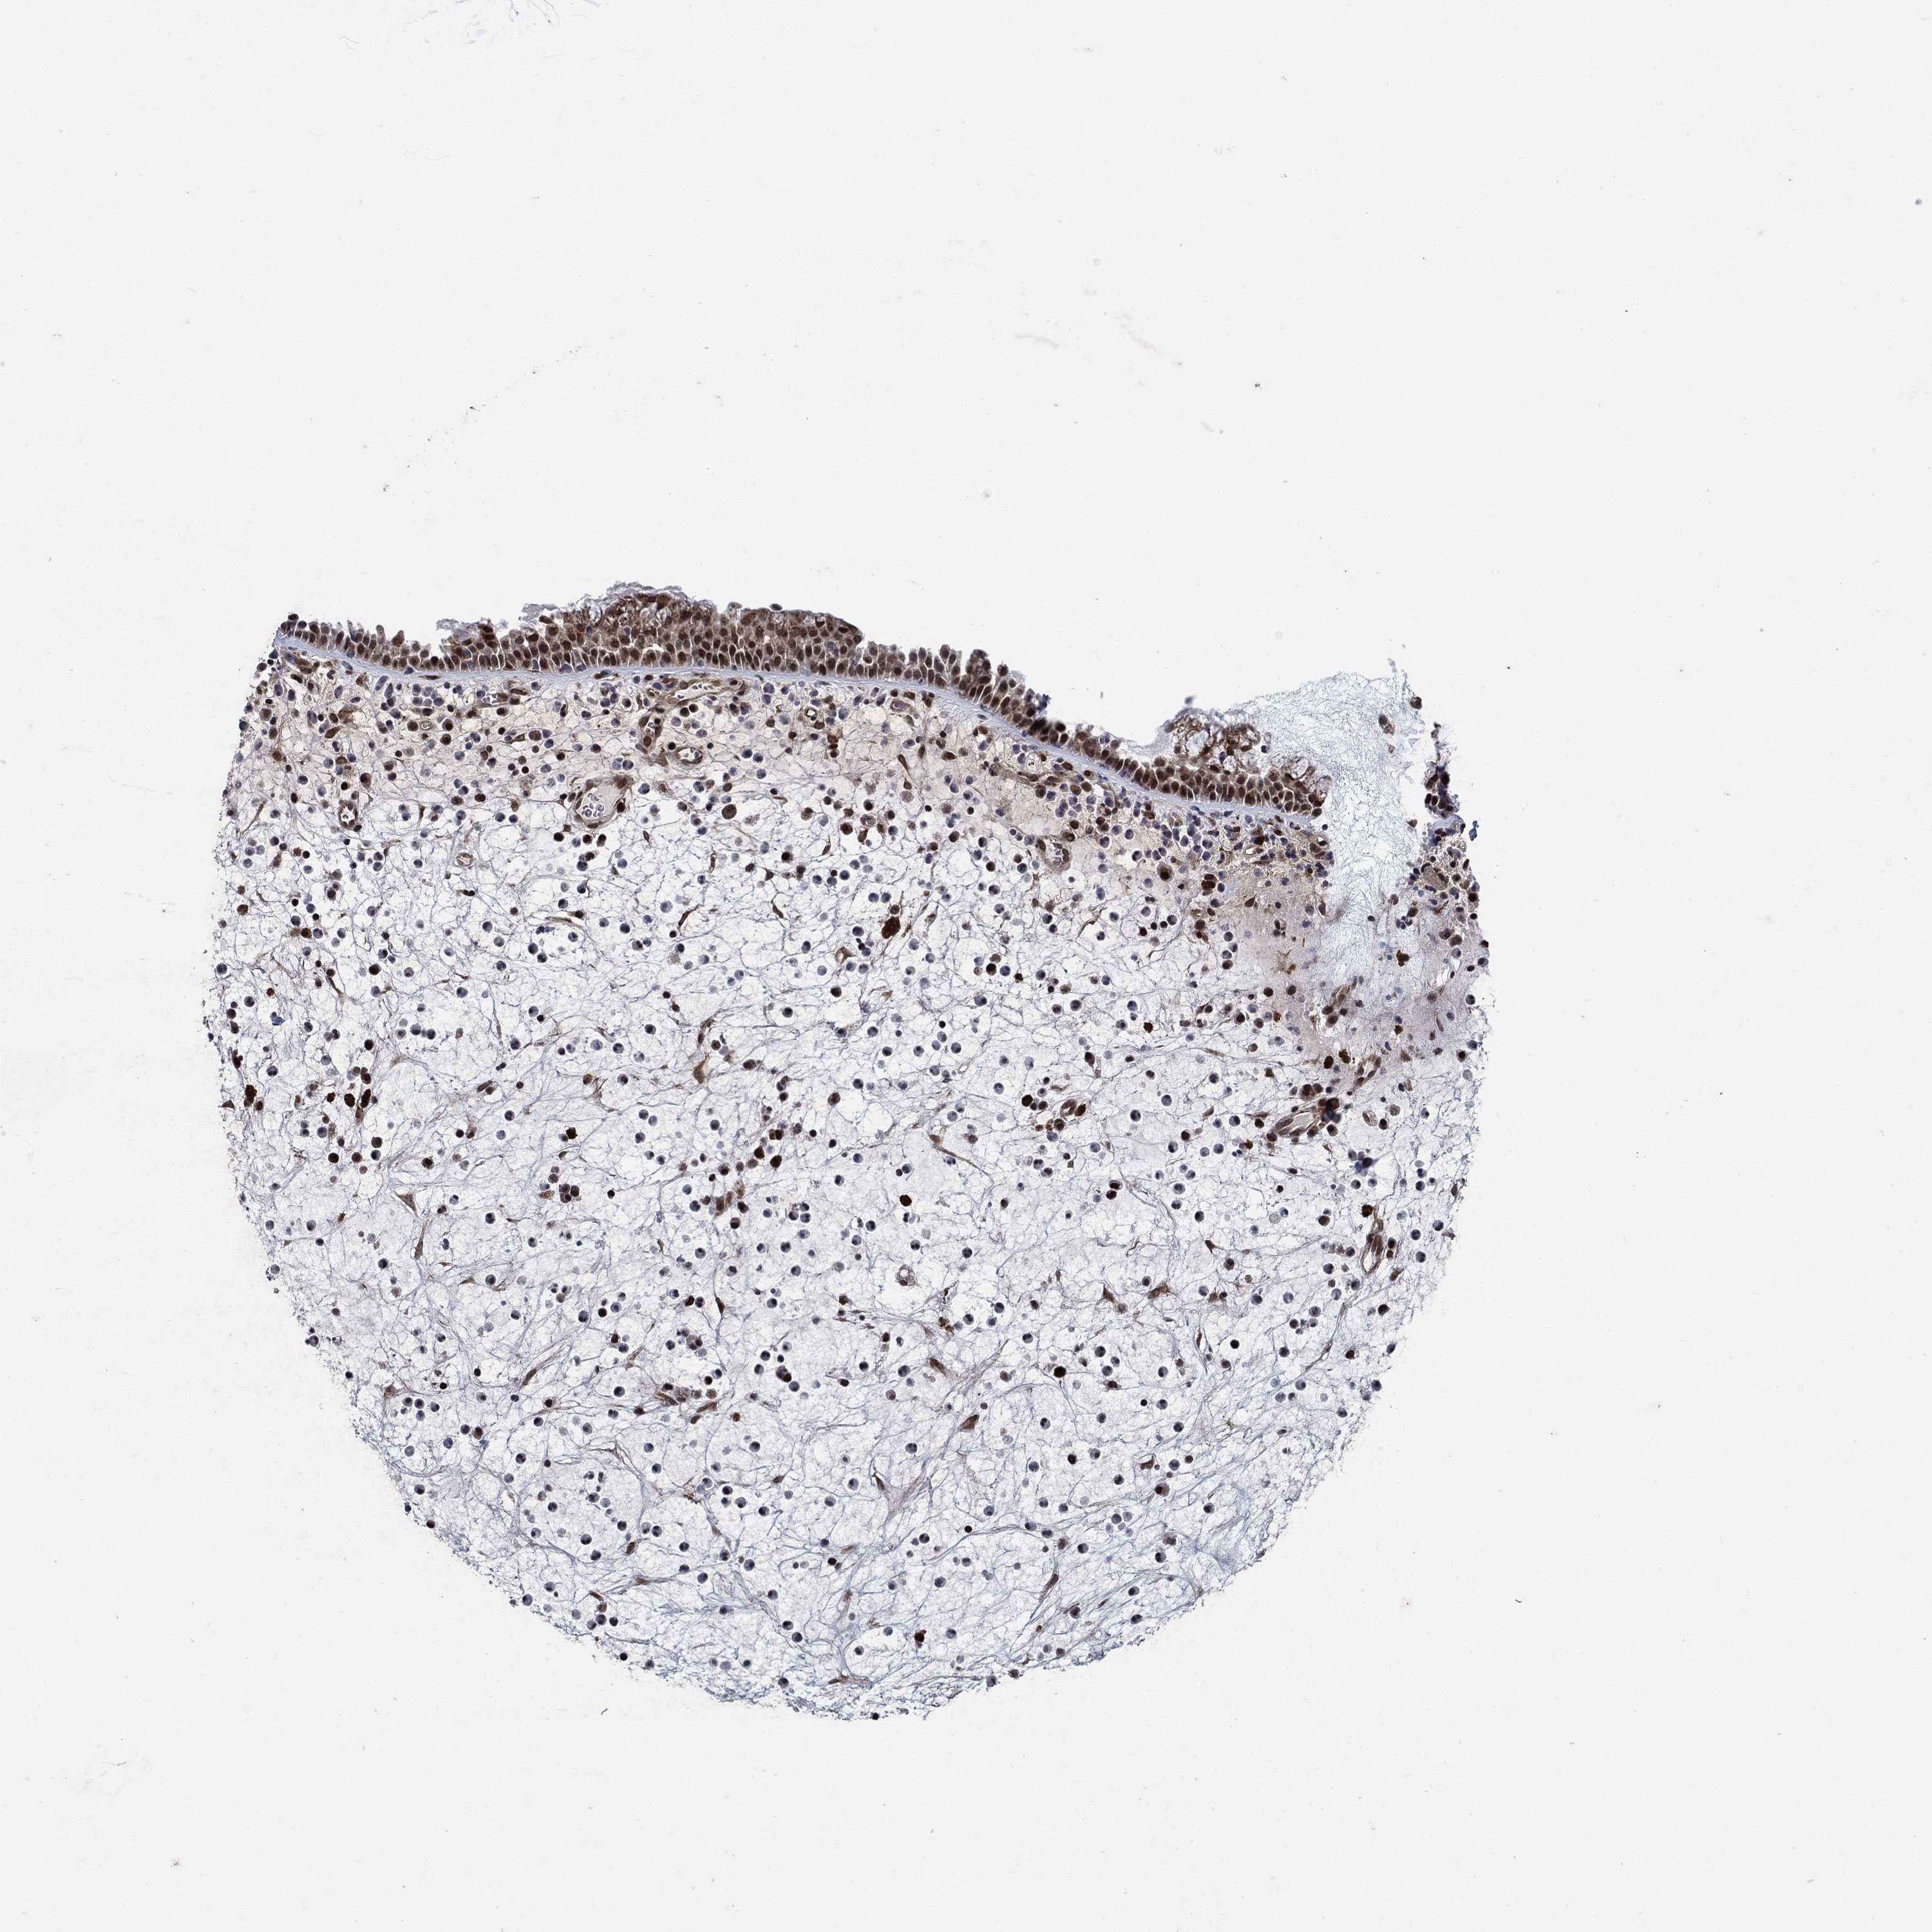

TISSUE PRIMARY DATA NASOPHARYNX Show tissue menu

NASOPHARYNX - Antibody stainingi

Antibody staining in the annotated cell types in the current human tissue is reported as not detected, low, medium, or high, based on conventional immunohistochemistry profiling in selected tissues. This score is based on the combination of the staining intensity and fraction of stained cells.

Each image is clickable and will lead to virtual microscopy that enables deeper exploration of all samples and also displays staining intensity scores, fraction scores and subcellular localization as well as patient and tissue information for each sample.

Antibody HPA055593

Respiratory epithelial cells High